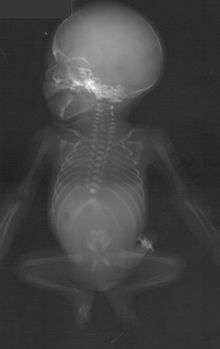

Sacral agenesis. | |

Caudal regression syndrome or sacral agenesis (or hypoplasia of the sacrum) is a congenital disorder in which there is abnormal fetal development of the lower spine—the caudal partition of the spine.[1]

This condition exists in a variety of forms, ranging from partial absence of the tail bone regions of the spine to absence of the lower vertebrae, pelvis and parts of the thoracic and/or lumbar areas of the spine. In some cases where only a small part of the spine is absent, there may be no outward sign of the condition. In cases where more substantial areas of the spine are absent, there may be fused, webbed, or smaller lower extremities and paralysis. Bowel and bladder control is usually affected.

There are four levels (or "types") of malformation. The least severe indicates partial deformation (unilateral) of the sacrum. The second level indicates a bilateral (uniform) deformation. The most severe types involve a total absence of the sacrum.